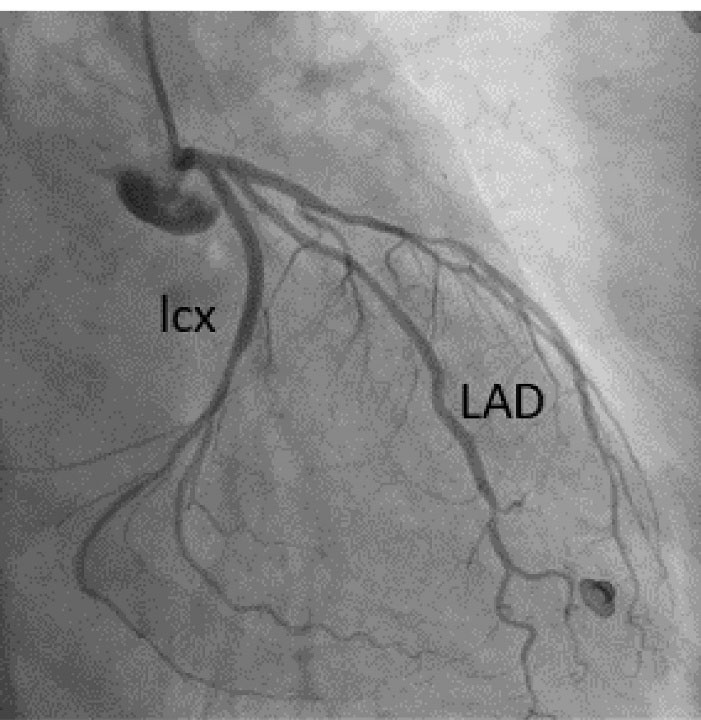

A 57-year-old lady with history of rheumatic mitral valve disease underwent mitral valve replacement by Saint Jude Medical Epic bioprosthesis in our high-volume mitral surgery center. Preoperative coronary angiography was non-significant except for a moderate stenosis of mid left anterior descending artery (LAD) (). The patient underwent coronary artery bypass grafting (CABG) using left internal mammary artery (LIMA) to LAD concomitantly with mitral valve surgery. The surgery was smooth with no postoperative complications. On serial postoperative electrocardiogram (EKG), there was no ST segment elevation or new significant ischemic changes compared to preoperative EKG. Routine postoperative echocardiogram showed good function of the mitral prosthesis and good global function of the left ventricle. Four weeks later, the patient started to have dyspnea, orthopnea and other symptoms of heart failure. EKG showed non-significant ST-T changes (). Echocardiography showed severely impaired left ventricle (LV) systolic function. Moreover, there was a localized hematoma adjacent to the right atrium without hemodynamic impact (). In light of these findings along with elevated troponin level, we decided to repeat coronary angiography. The later showed complete occlusion of the proximal LCX () and stenosis of the LIMA -LAD anastomosis. A PCI strategy was successful for LIMA-LAD stenosis () but difficult for LCX lesion; after crossing the lesion using work-horse wire, and use of different size non-compliant and compliant balloons, there was continuous recoil after balloon deflation (). The trial of angioplasty and stenting was failed with no recuperation of distal flow. Therefore, we suspected surgical complication with mechanical compression of the circumflex coronary artery most probably by encircling suture loop, in addition to stenosis of the LIMA-LAD. Furthermore, the retro atrial hematoma might be caused by epicardial coronary artery injury. The procedure was then stopped and the patient was kept on medical treatment. On follow up visits, there was complete resolution of the atrial hematoma, and a significant improvement of LV function on standard heart failure treatment.

Figure 1. Coronary angiography RAO caudal view; a moderate stenosis on mid LAD is seen, RAO; right anterior oblique, LAD; left anterior descending artery.